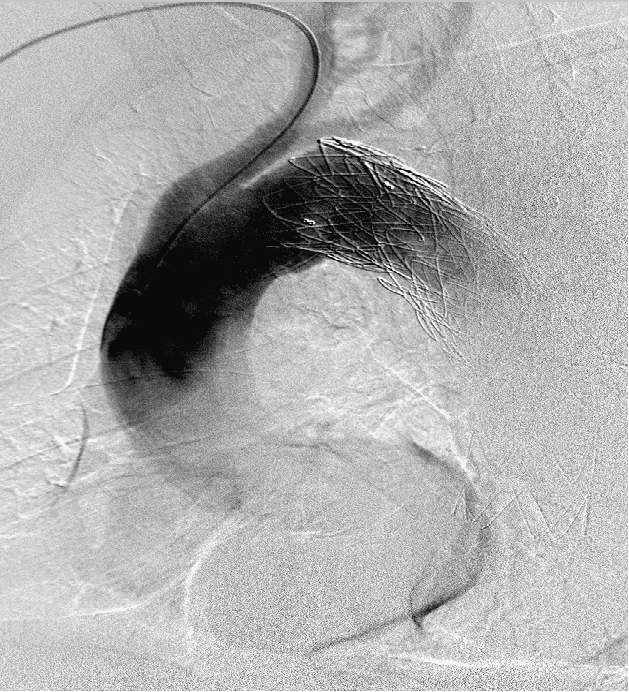

男, 49岁,急性夹层 。2018年11月TEVAR。一月后复查:RTAD 。 2019年1月双开窗。2019年4月2日 复查,结果良好。

RTAD治疗的“金标准”仍是开放修复。7例RTAD患者转心外科行全弓置换+支架象鼻,7例痊愈。腔内修复在Z0区再次TEVAR很可能再次RTAD。